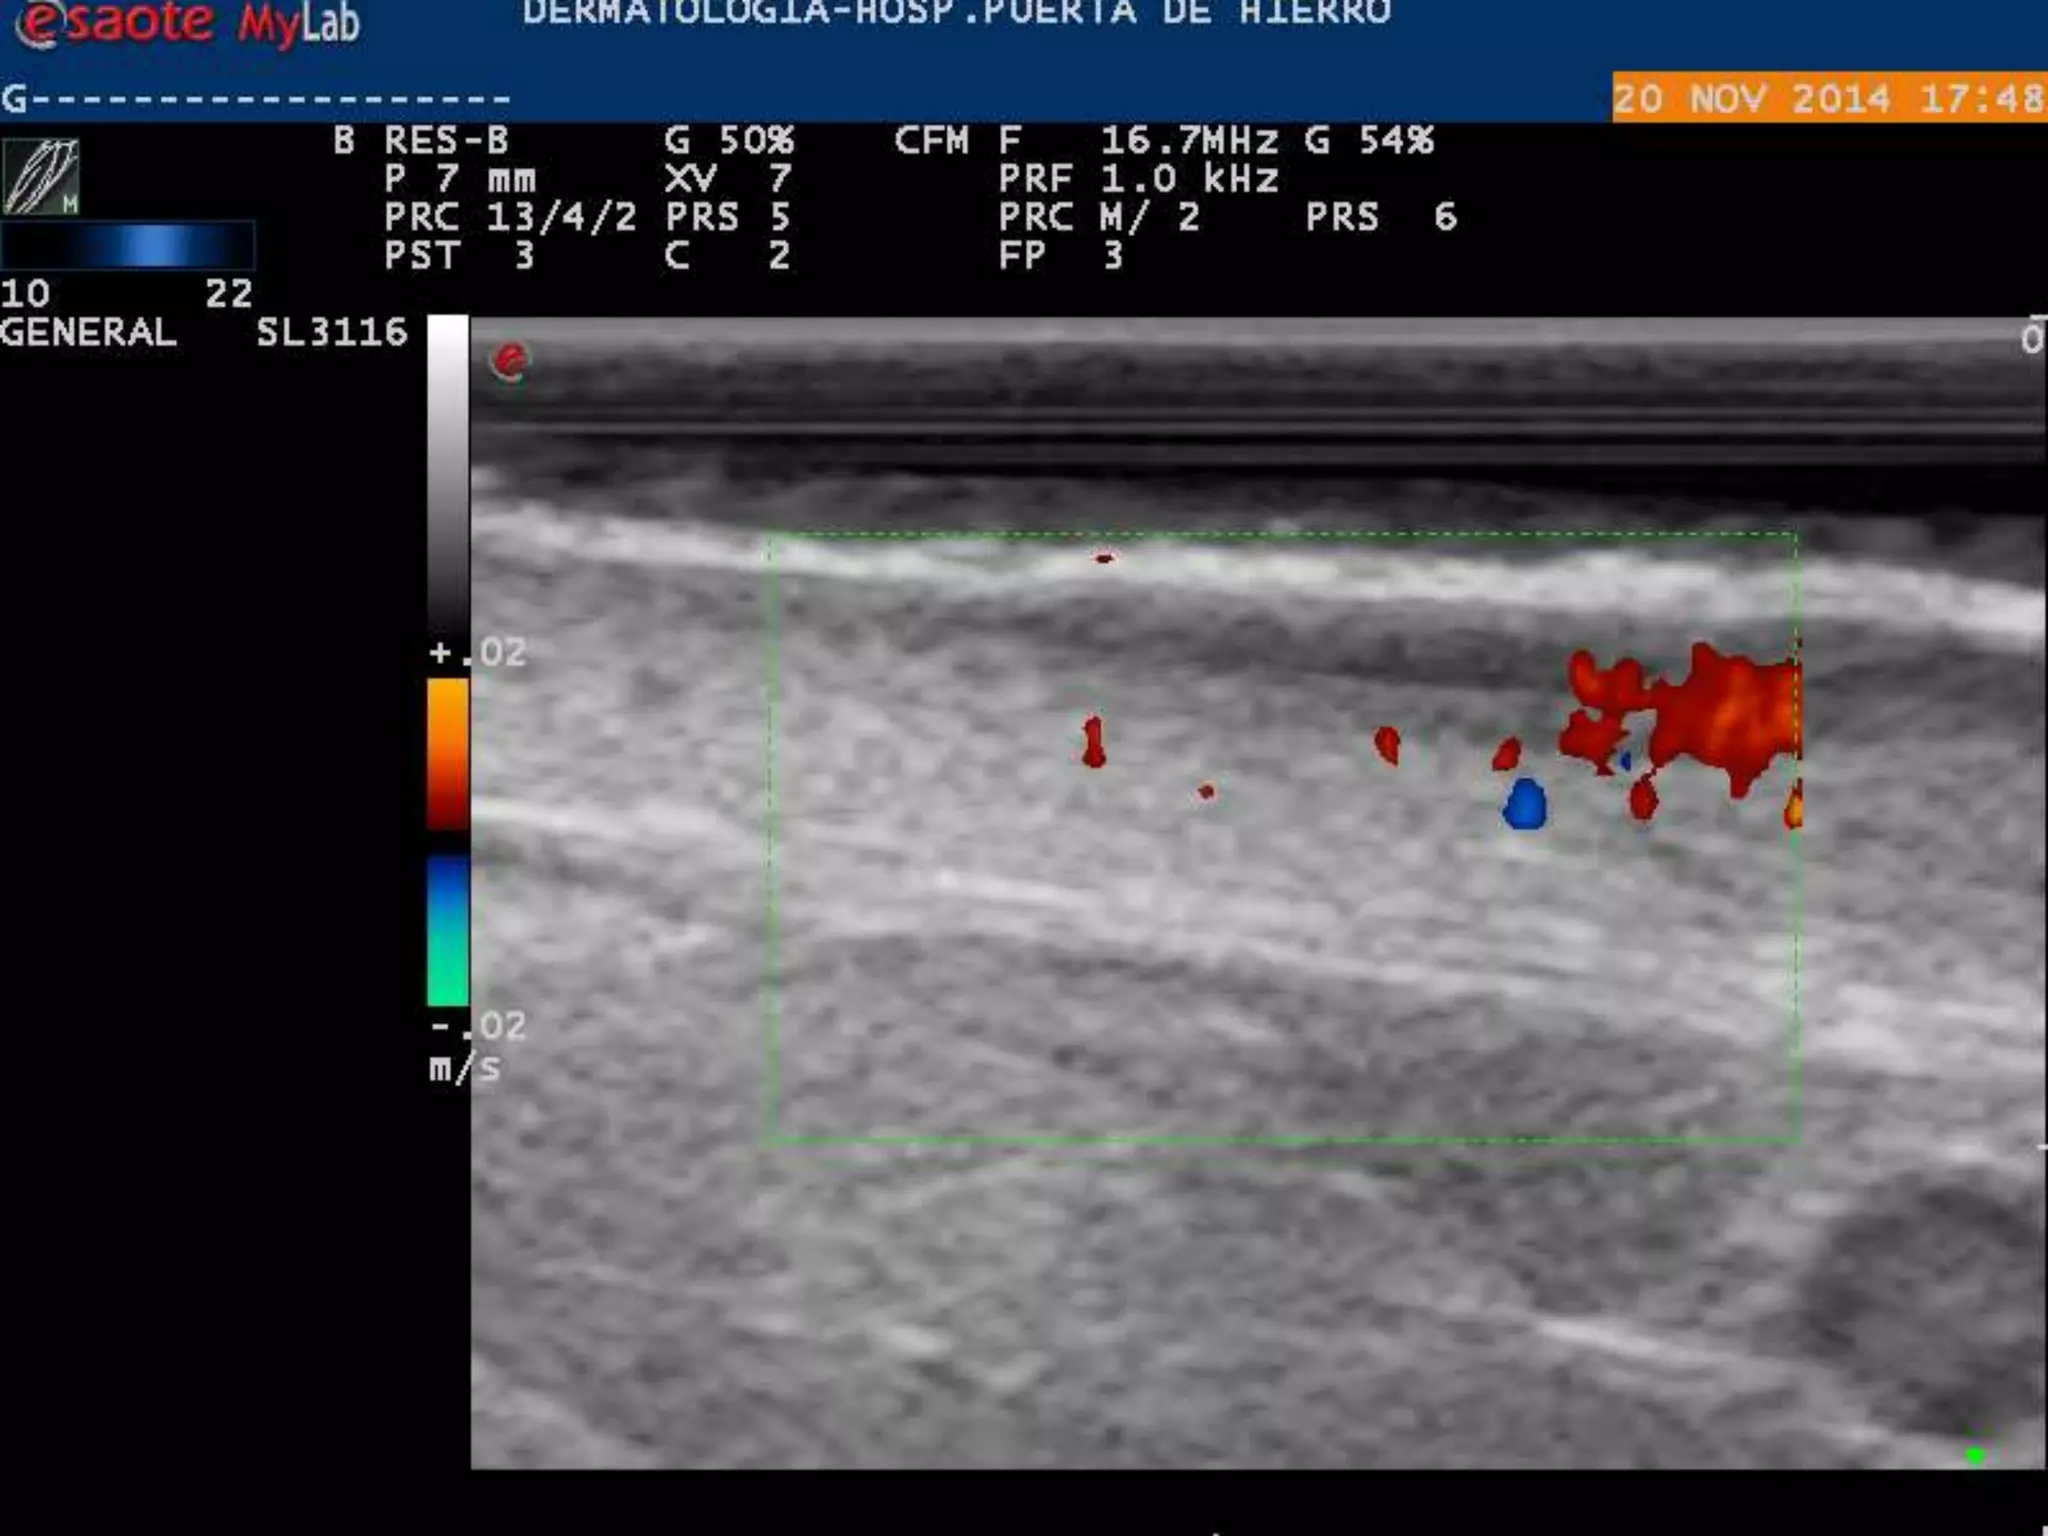

PLACA DE PSORIASIS

INFLAMADO

LOCALIZACION DE INFLAMACION

DERMIS/SUBDERMIS

HIDRADENITIS SUPURATIVA

DERMIS

ROSACEA